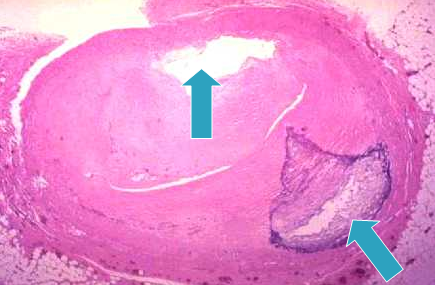

Atheroma Coronary Artery:

Atheroma with Thrombosis:

White infarct:

Solid organs like kidney and liver with arterial occlusion

Here the solidness of tissue limits the amount of hemorrhage that can seep into area of ischemic necrosis from adjoining capillaries.